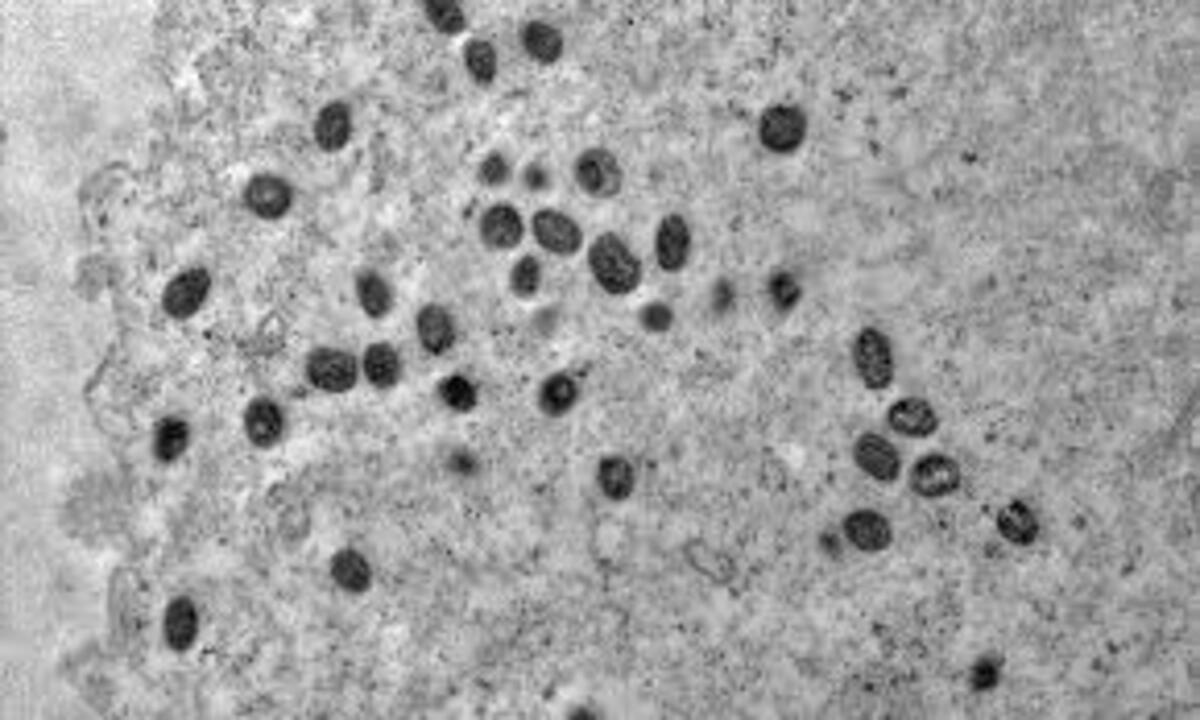

A Mpox é causada por um vírus da mesma família da varíola e é transmitida principalmente pelo contato direto com lesões na pele, além de secreções respiratórias e saliva.